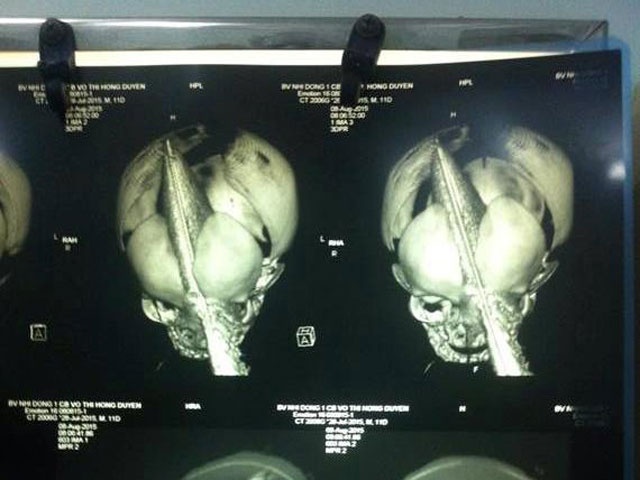

Ngay sau đó các bác sĩ nhanh chóng đến phòng bệnh cấp cứu cho cháu bé và chuyển lên bệnh viên Nhi đồng 1 cấp cứu. Tai họa ập đến quá bất ngờ, chị Duyên cũng hoảng loạn, ngất đi và được các bác sĩ chăm sóc đặc biệt.

| Gia đình nạn nhân cũng không loại trừ nghi vấn người phụ nữ này có thể muốn bắt cóc cháu bé nhưng bị phát hiện liền tấn công sản phụ, gây ra vết thương trên vùng trán cháu bé. Ảnh: Bệnh viện Nhi đồng 1. |